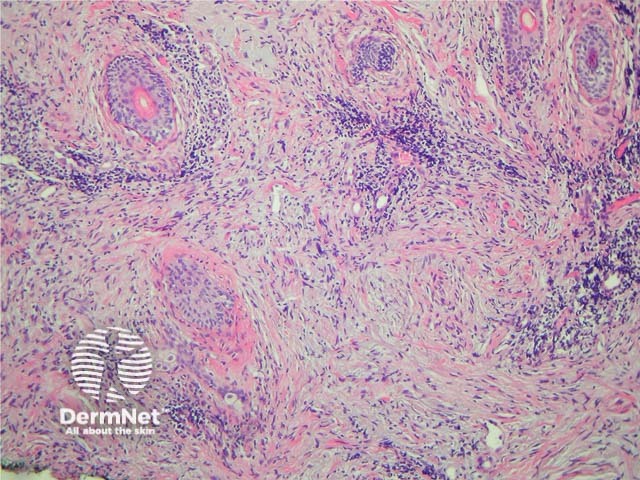

Desmoplastic melanoma (DM) is characterised by tumour cells which produce a fibromucinous matrix. Over half of cases occur on the head and neck. Clinically these are slow growing often non-pigmented lesions, which may resemble scar tissue. Some cases probably start their evolution as lentigo maligna melanoma.

On histology there are spindle-shaped tumour cells within the dermis and subcutis surrounded by mature collagen bundles. The relative proportion of tumour cells to surrounding stroma is variable. When there are an abundance of tumour cells the lesion may be reported as spindle-cell melanoma. These tumours are usually deeply infiltrative and accurate identification of depth of invasion often relies on the use of special stains. Scattered lymphoctyes and plasma cells within the tumour may be a clue to diagnosis. Less cellular variants may be mistaken for dermatofibroma. See Figures 24, 25.

These tumours are often negative with immunohistochemical studies for HMB-45 and Melan-A but S100 or SOX10 can be very helpful because these are practically always positive (see figure 26).

Neurotropic melanoma describes a variant of desmoplastic melanoma where there is infiltration of nerves and tumour cells can be seen arranged in a concentric fashion around nerve fibres. This variant has a high rate of local recurrence.

Figure 24

Figure 25